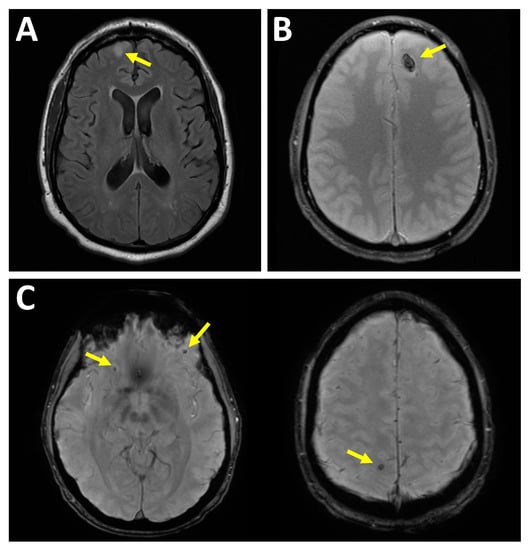

Figure 2.

Intra-axial injury patterns. (A) Nonhemorrhagic brain surface contusion. Sixty-six-year-old male fell and hit head on concrete with subsequent loss of consciousness. Axial T2-weighted fluid-attenuated inversion recovery (FLAIR) image demonstrates focal increased signal within the right frontal lobe cortex. (B) Hemorrhagic brain contusion. Twenty-four-year-old male who fell and hit his head after playing basketball with subsequent loss of consciousness. Axial T2*-weighted gradient echo (GRE) image demonstrates focal region of hypointense signal in the left front lobe. (C) Diffuse axonal injury. Forty-year-old male after falling from multiple flights of stairs. Two axial T2* susceptibility-weighted imaging (SWI) images demonstrate multiple foci of hypointensity consistent with punctate hemorrhage at the gray-white junctions. This is a consequence of shearing forces.

In an intraparenchymal hematoma, the hemorrhage is within the brain tissue itself. Intraparenchymal hemorrhages are commonly due to contusions and axonal injuries. The mechanisms of injury in diffuse axonal injury (DAI) are likely more complex than only primary mechanical axotomy in the setting of trauma [,,]. Diffuse axonal injury is a shearing-type injury to axons typically from a significant rotational acceleration/deceleration force []. On MRI, DAI injuries can be seen as hyperintense signal on a T2-weighted sequence and, if associated with hemorrhage then hypointense signal on T2*-weighted sequence, at the corticomedullary junction, corpus callosum, internal capsule, brainstem, and cerebellum []; see Figure 2.